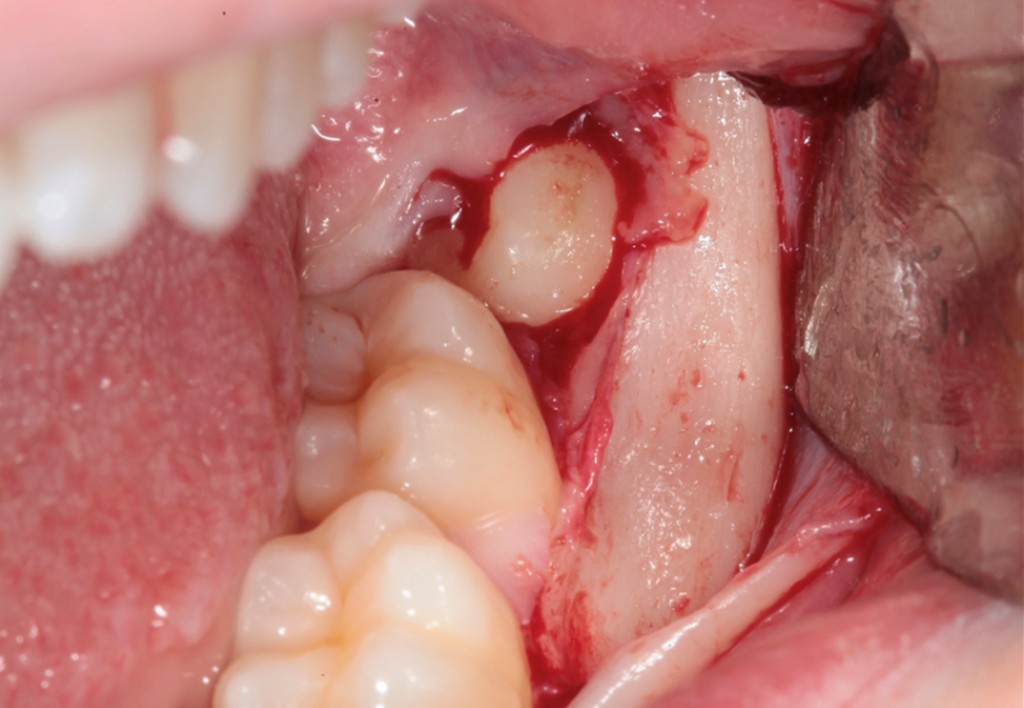

► Tecniche chirurgiche per elementi complessi

Approccio ad elementi inclusi, parzialmente inclusi, in arcata o sovrannumerari, con tecniche atraumatiche e sicure.

► Socket preservation

Strategie per mantenere il volume della cresta ossea e dei tessuti molli, con focus su biomateriali e tempi di guarigione.

Galleria fotografica